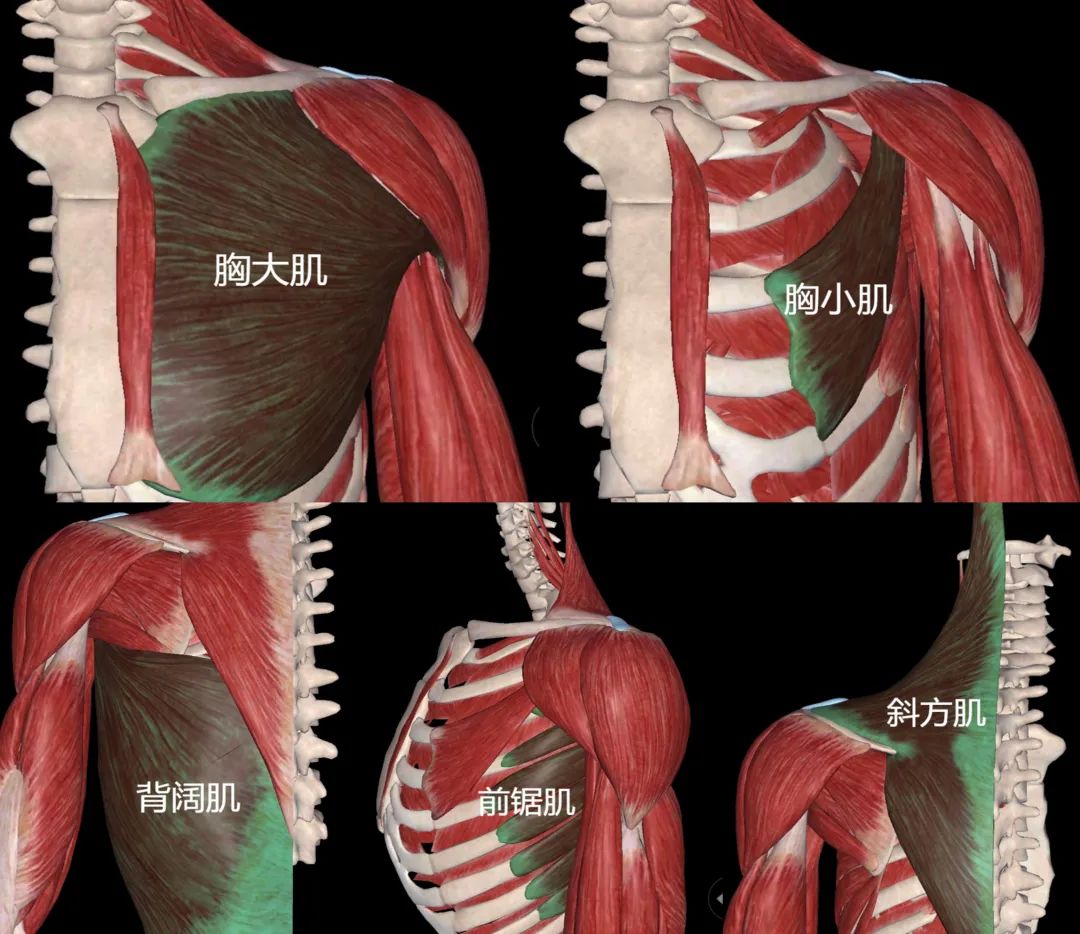

神經(jīng)肌肉再教育需要特別關(guān)注的肌肉包括:肩袖(特別是外肩袖——岡下肌和小圓肌)、背闊肌、前鋸肌、斜方肌各束(上/中/下)、胸大肌和胸小肌。并且,在肩關(guān)節(jié)活動(dòng)中肩胛骨的上旋、外旋和后仰所表現(xiàn)的方式和時(shí)機(jī)也同樣不能忽視。